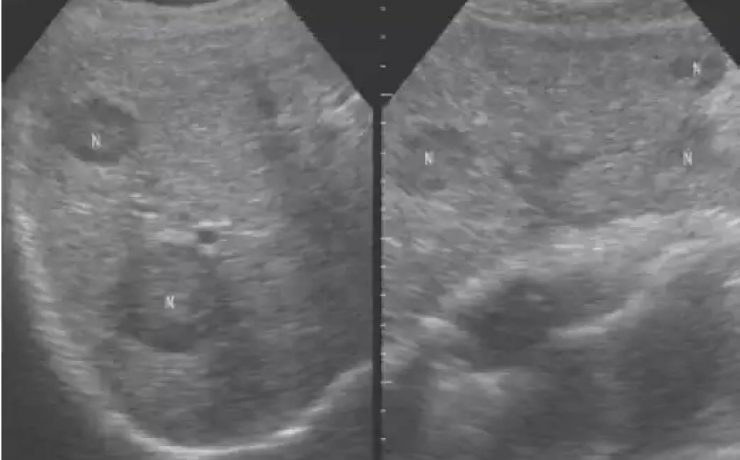

Patologías benignas de la próstata: prostatitis e hiperplasia prostática benigna.

Se realiza revisión detallada de la anatomía prostática y los principales factores que influyen en el aumento de volumen de la glándula prostática de origen patológico con diversas etiologías. Presentando como principales patologías la prostatitis y la hiperplasia prostática benigna. El término prostatitis incluye un conjunto de síntomas o disturbios